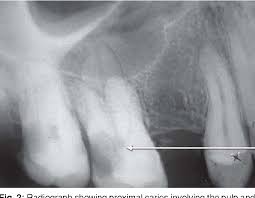

Pdf Diagnostic Value Of Dental Pulp Stones In The Early Diagnosis Of Ischemic Heart Diseases

Dental Pulp Stones In The Early Diagnosis Of Ischemic Heart Diseases

The number of patients for whom the ratio of teeth with pulp stone to. 4 Various theories regarding the etiological factors behind the occurrence of pulp stones have. The purpose of this study is to investigate the association of dental pulp stones with ischemic heart disease. The dental pulp in the root canal in patients with confirmed heart diseases they may be susceptible to heart attacks. Free pulp stones are available within the pulp tissue mass because they are the most typically observed form on radiographs. In individualswithout IHD 5 of the teeth showed pulp stone while this rate was 45 9 times in CVD patients. An intriguing prevalence study.